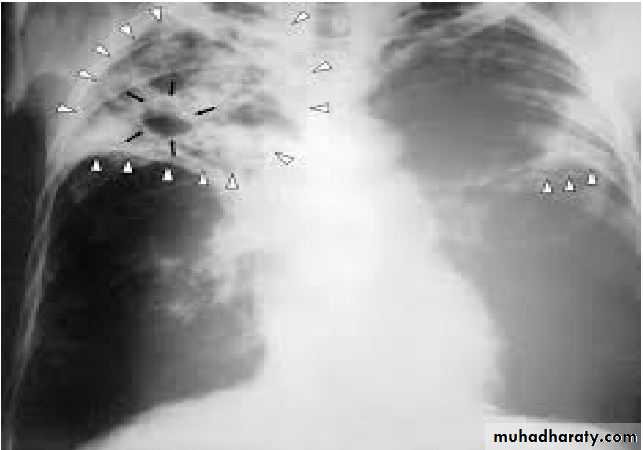

Diagnosis